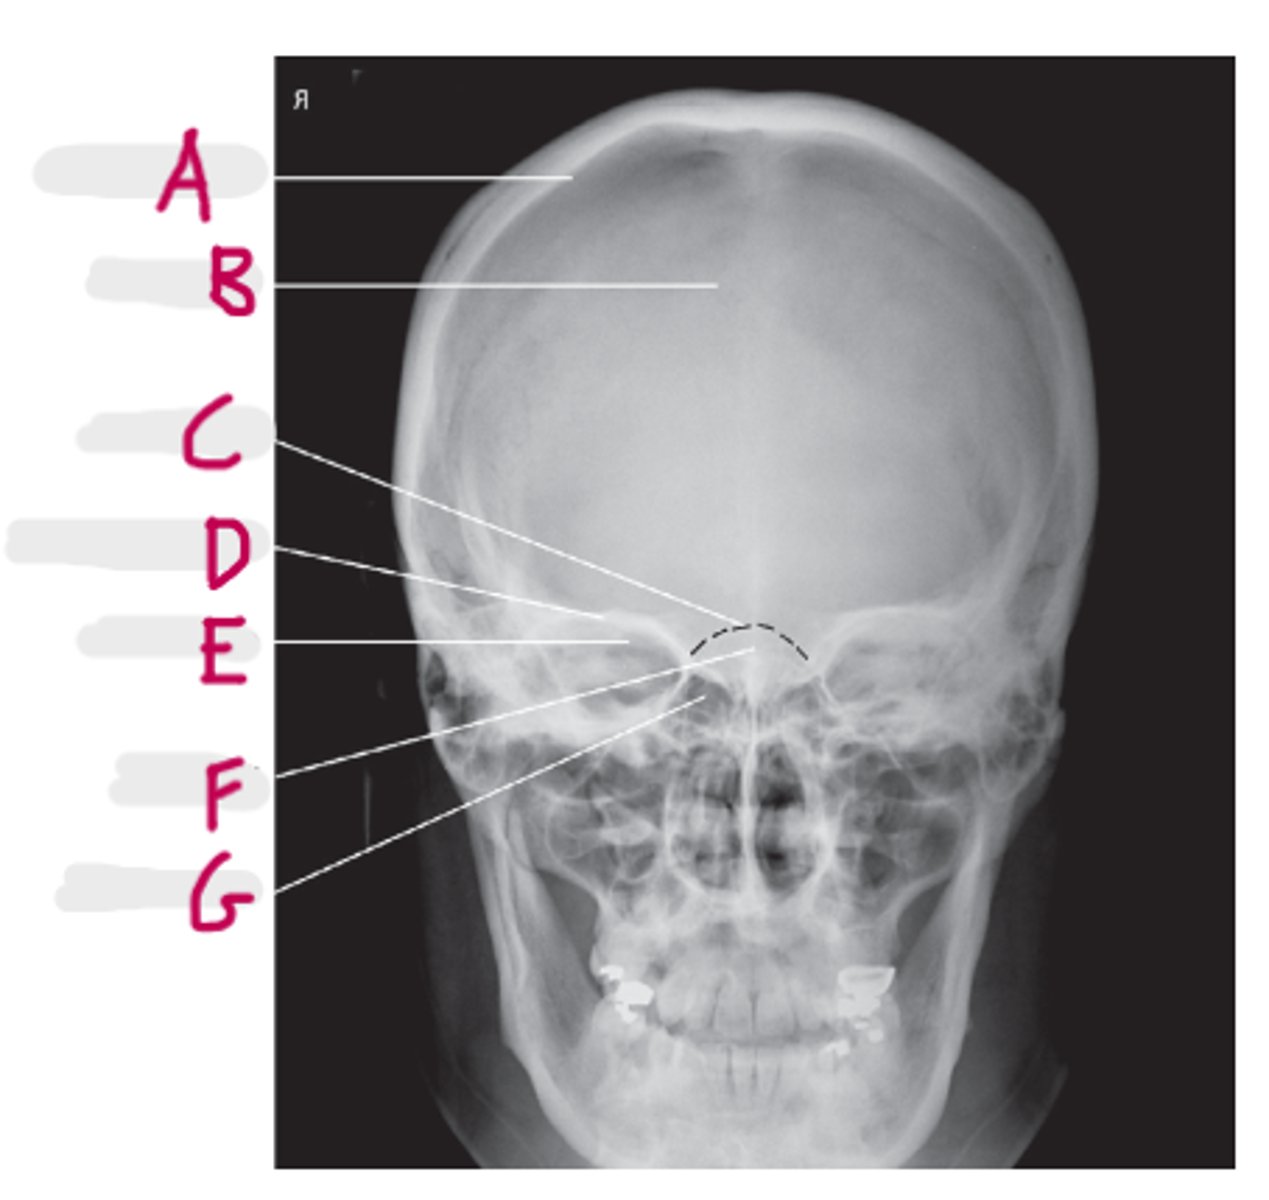

Parietal bone

A

Frontal bone

B

Dorsum sella

C

Supraorbital margin

D

Petrous ridge

E

Crista galli

F

Ethmoidal sinus

G